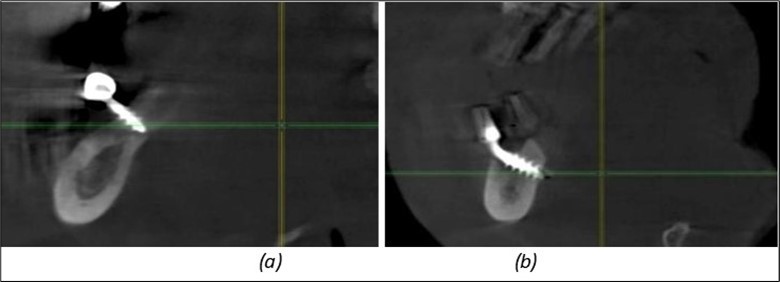

Figure 12.Implants fixed distally in quadrant 4 with fixation at the level of the mylohyoid line: (a) The most distal implant fixed in unaffected bone from the previous restoration; (b) The implant fixed in the area where the two stage implant was removed.

Implants fixed distally in quadrant 4 with fixation at the level of the mylohyoid line: (a) The most distal implant fixed in unaffected bone from the previous restoration; (b) The implant fixed in the area where the two stage implant was removed.